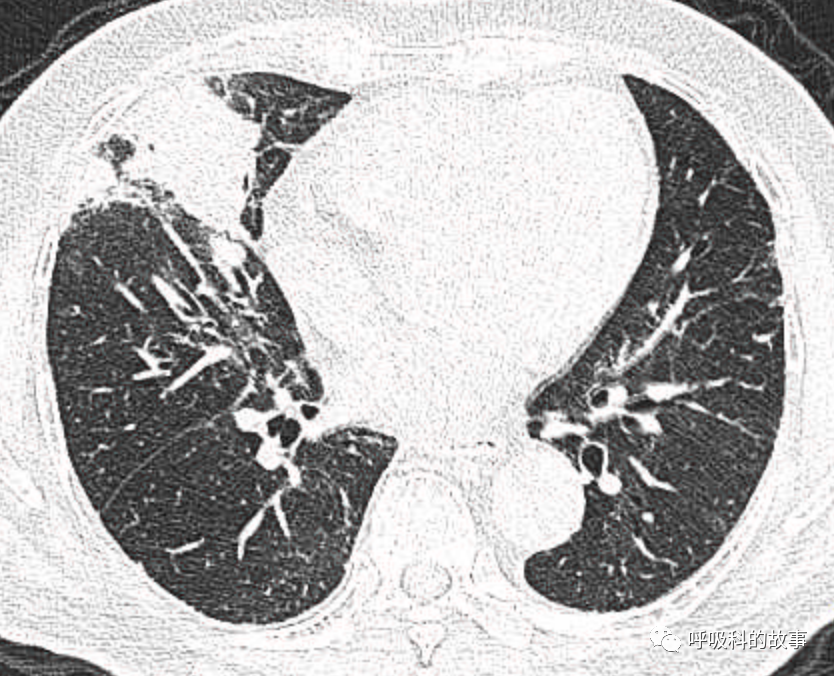

可是就在今年初,患者曾住在某院某科室,因为其他内科疾病住院。当时肺部CT也发现了在右中叶内侧段的高密度实变影,由于影像很类似肺炎,因此当成肺炎治疗。

图12-14:该患者各个角度的影像图像

(上下滑动查看全部图片)